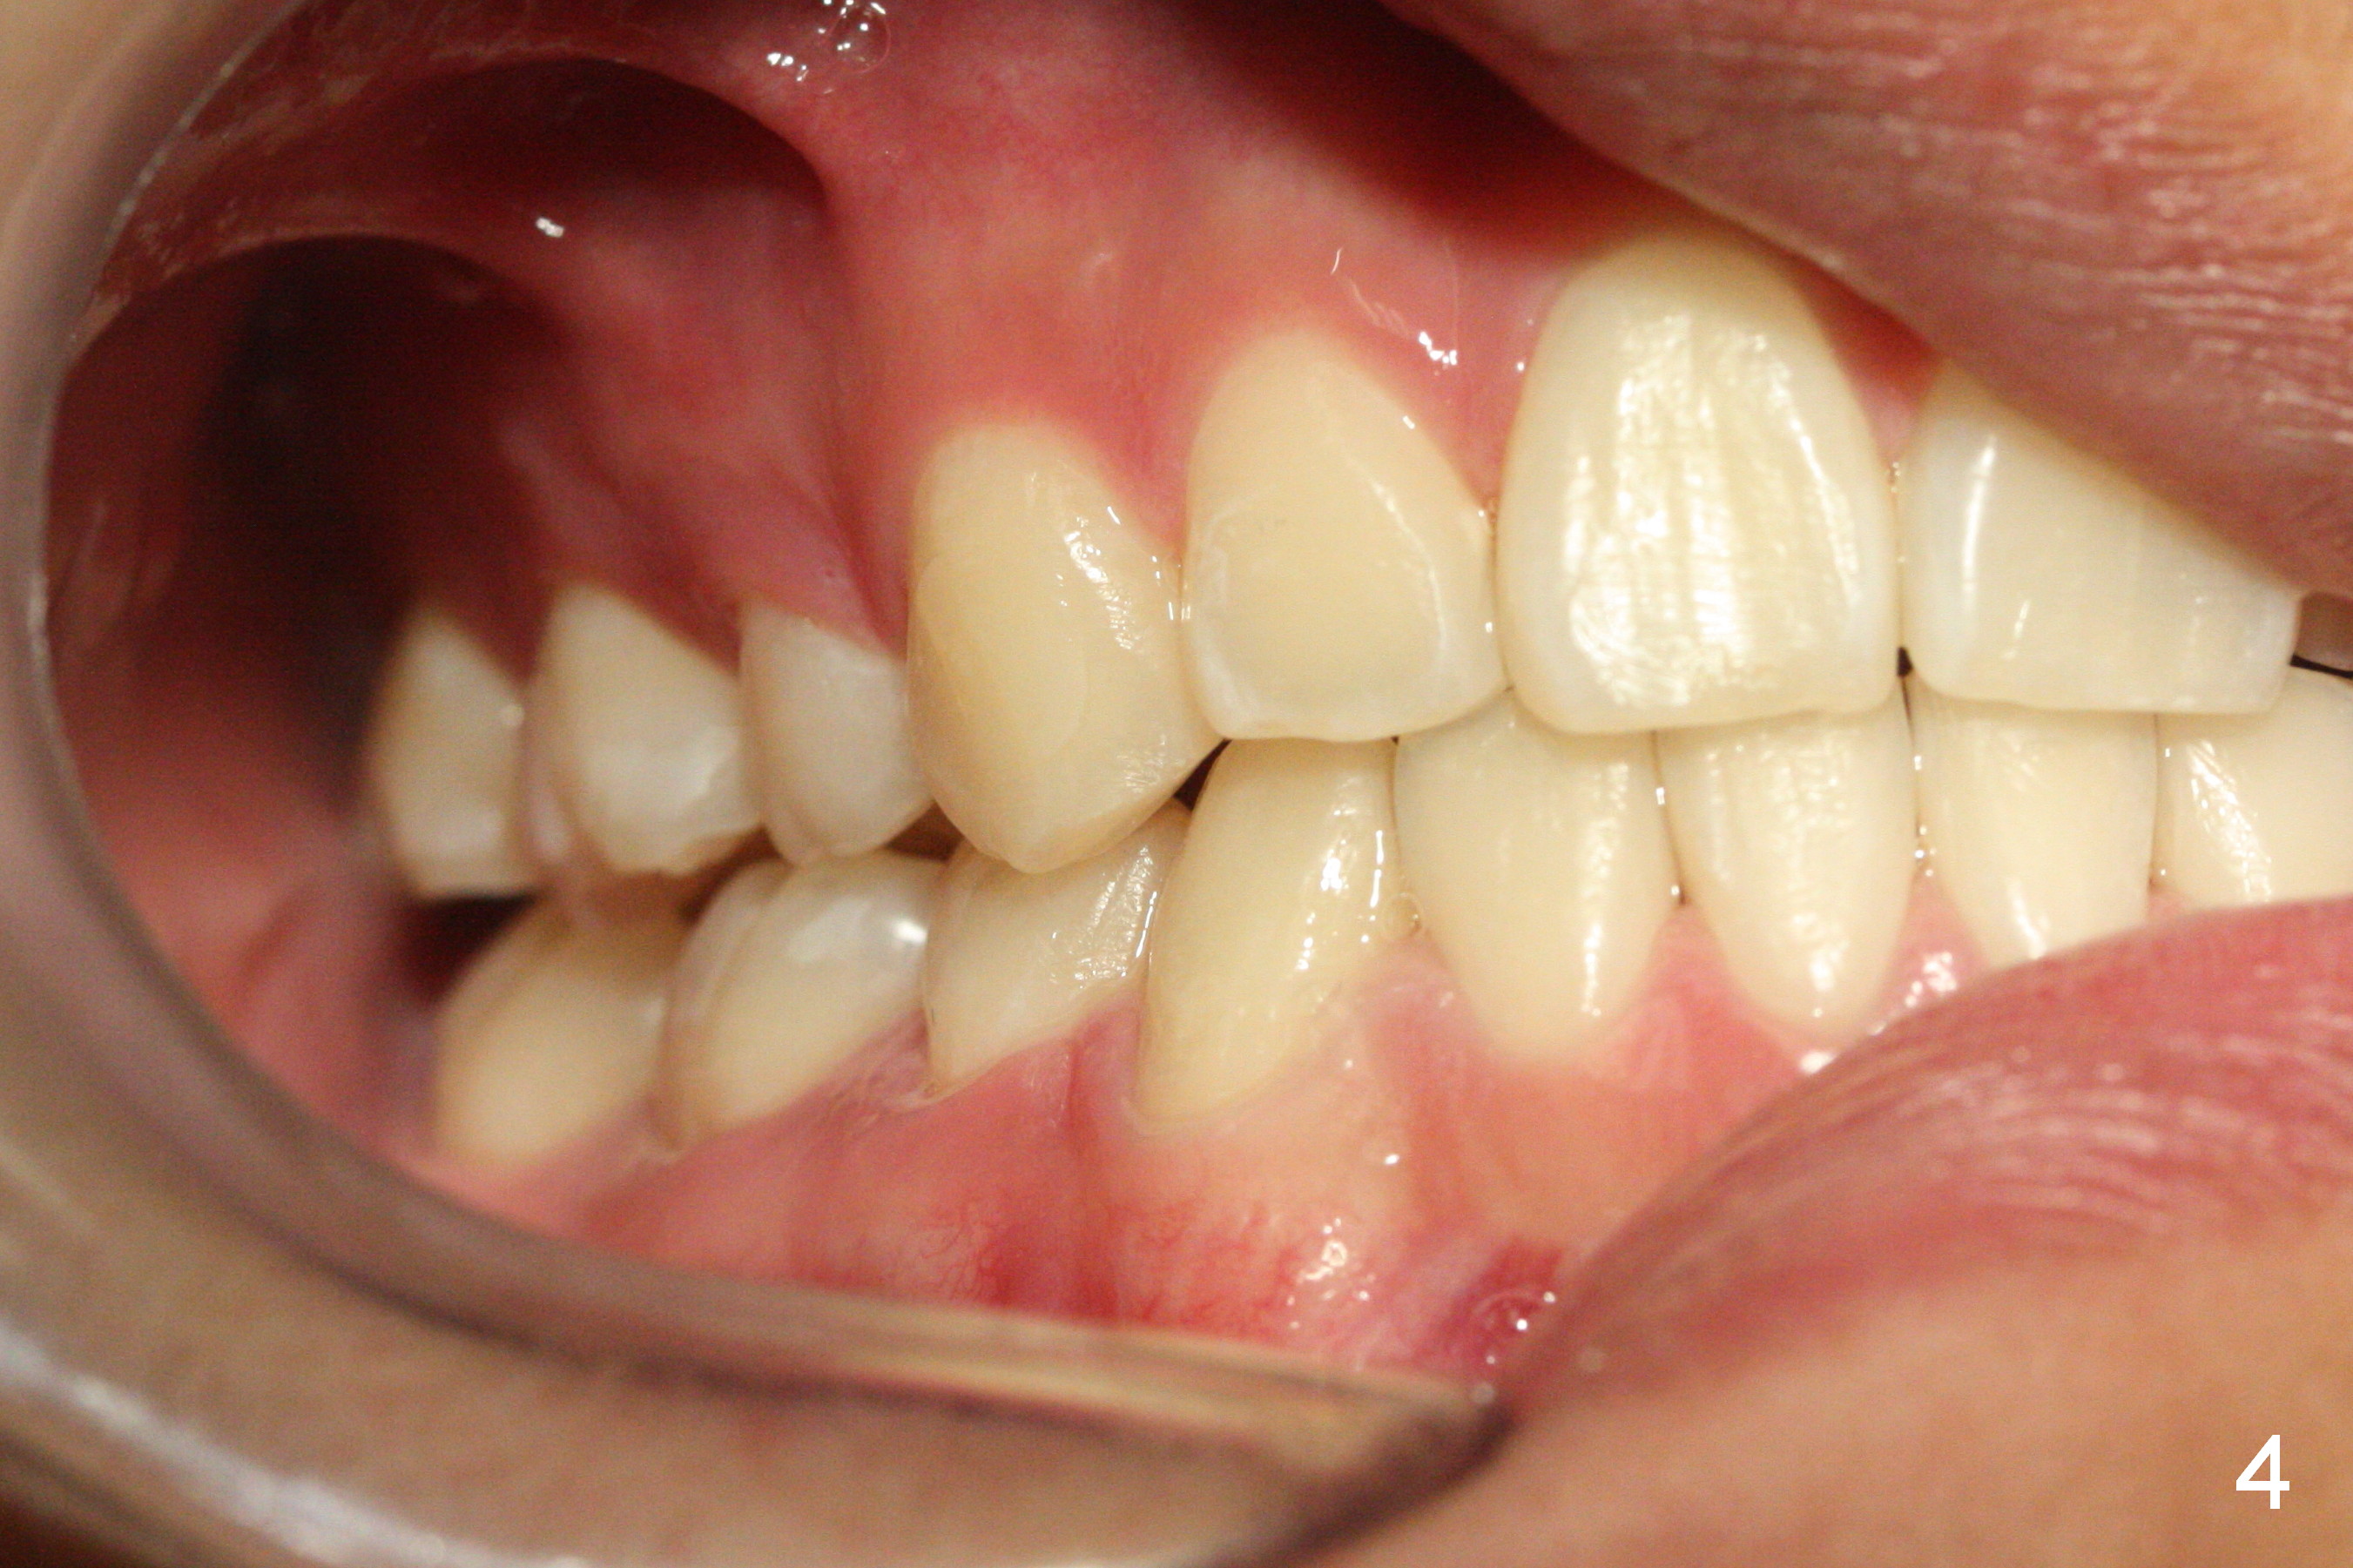

How to Take Before and After Photos for Orthodontics

When taking photos for the lateral view of the occlusion (Fig.3, retract the corner mouth as back as possible using proper sized cheek retractors (single or double, child or adult) or a mouth mirror. The focus should be on the posterior teeth, showing interdigitation. That is move the camera to the side of the face.

It would be nice to take direct shot of the upper and lower arches if the indirect one is difficult to obtain.